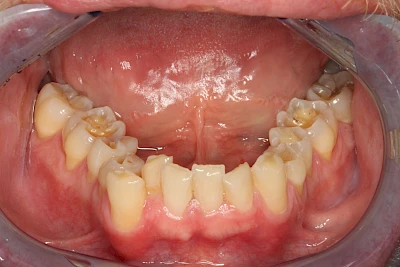

- Abnutzung durch Kauen (Abrasion) oder duch durch übermäßiges Knirschen bzw. Pressen (Attrition)

- Säurebedingte Auswaschung (Erosion)

- Knirschen bzw. Pressen und ungünstige Putztechnik (Druck): keilförmige Defekte